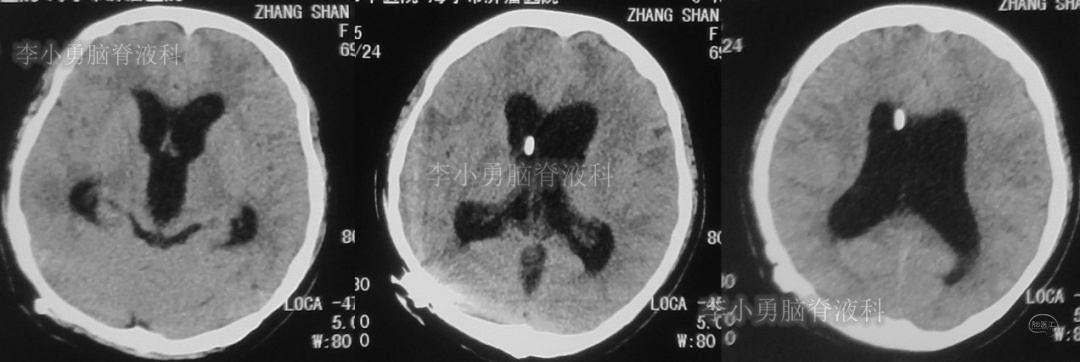

此次分流泵调压后1个月,即2018年12月11日,患者第3次出现头痛,而且头痛逐渐加重并昏迷,急到当地的第1家医院行头颅CT(图-7)见脑室从缩小又变成扩大状态。

图-7:2018年12月11日头颅CT

第3次调压后18天,即2018年12月29日,患者恢复好,在当地第1家医院复查头CT(图-8)见脑室明显缩小。

图-8:2018年12月29日头颅CT